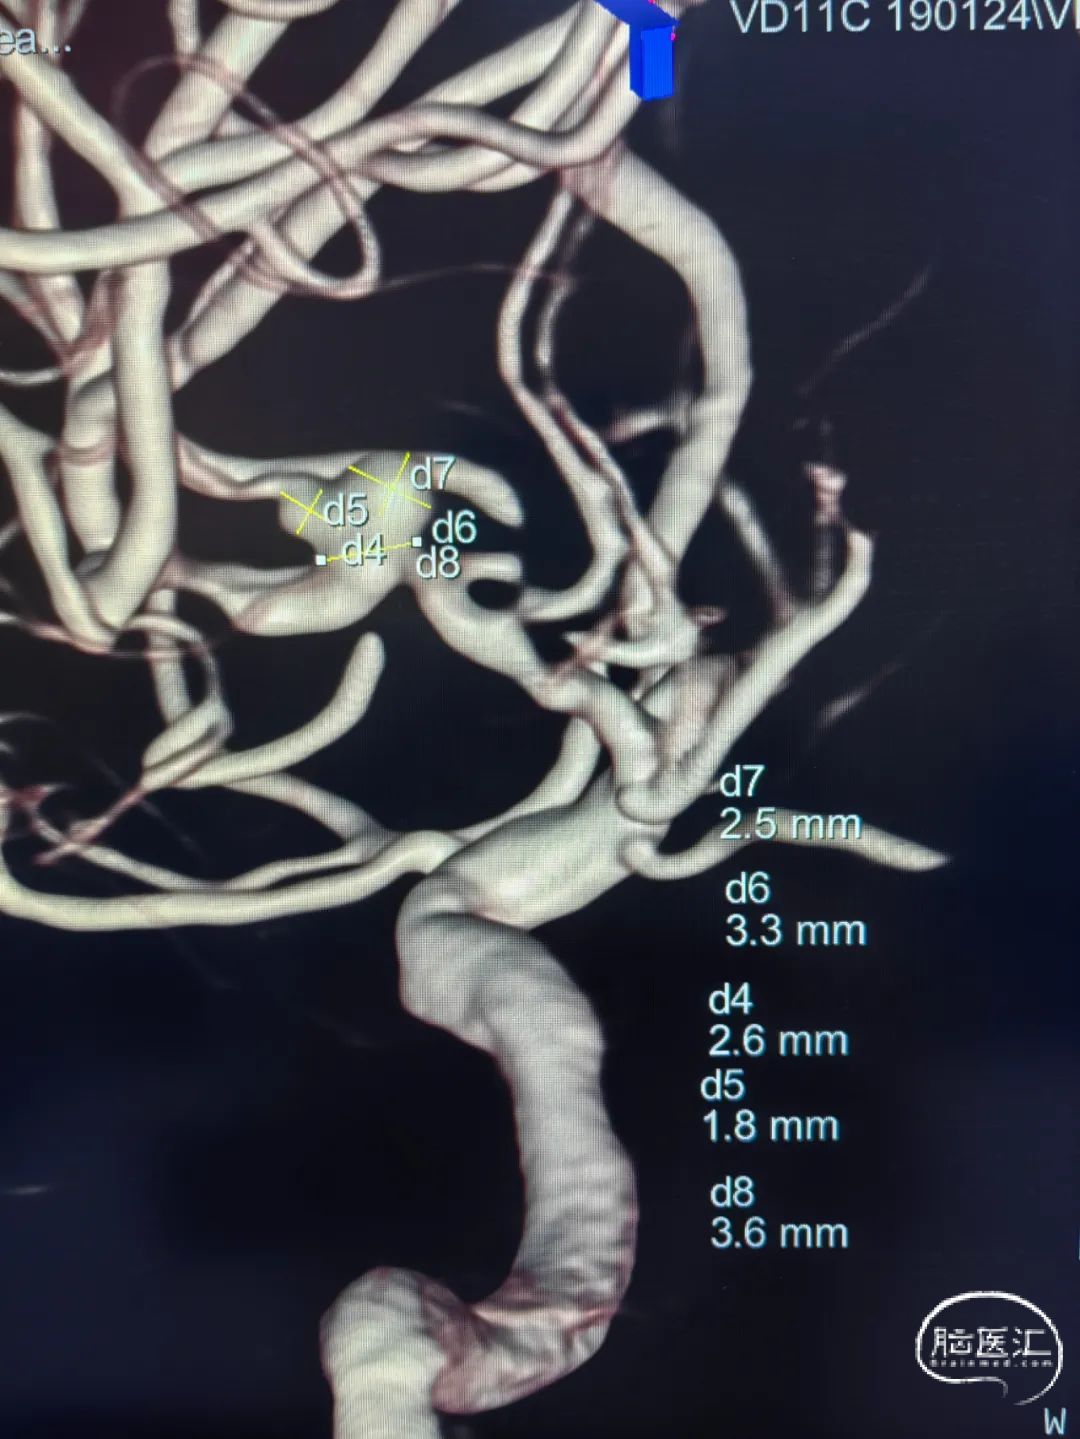

术前影像

左侧大脑中动脉M2段动脉瘤,前交通动脉瘤栓塞术后。

更换6F 长鞘,使用泥鳅导丝将6F 115cm Tethys®中间导引导管送至C1段,使用14微导丝及SL-10微导管将6F 115cm Tethys®中间导引导管送至C5段。

释放张力,后释放激光雕刻开环支架 3.0*21mm横跨动脉瘤颈,继续填塞Jasper®弹簧圈 1.5*3一枚、1.5*2两枚致密栓塞。

颅内动脉瘤的介入手术治疗越来越普及,对于颅内远端动脉瘤、载瘤动脉迂曲、行径血管迂曲的病人,中间导引导管的柔韧性、高到位性以及整体系统的支撑性成为动脉瘤栓塞成功的关键因素。本例手术为一例M2段动脉瘤,位置较远且入路行径动脉迂曲,Tethys®中间导引导管的通过性以及相对位置的支撑性保障了支架辅助弹簧圈顺利治疗该例病变。